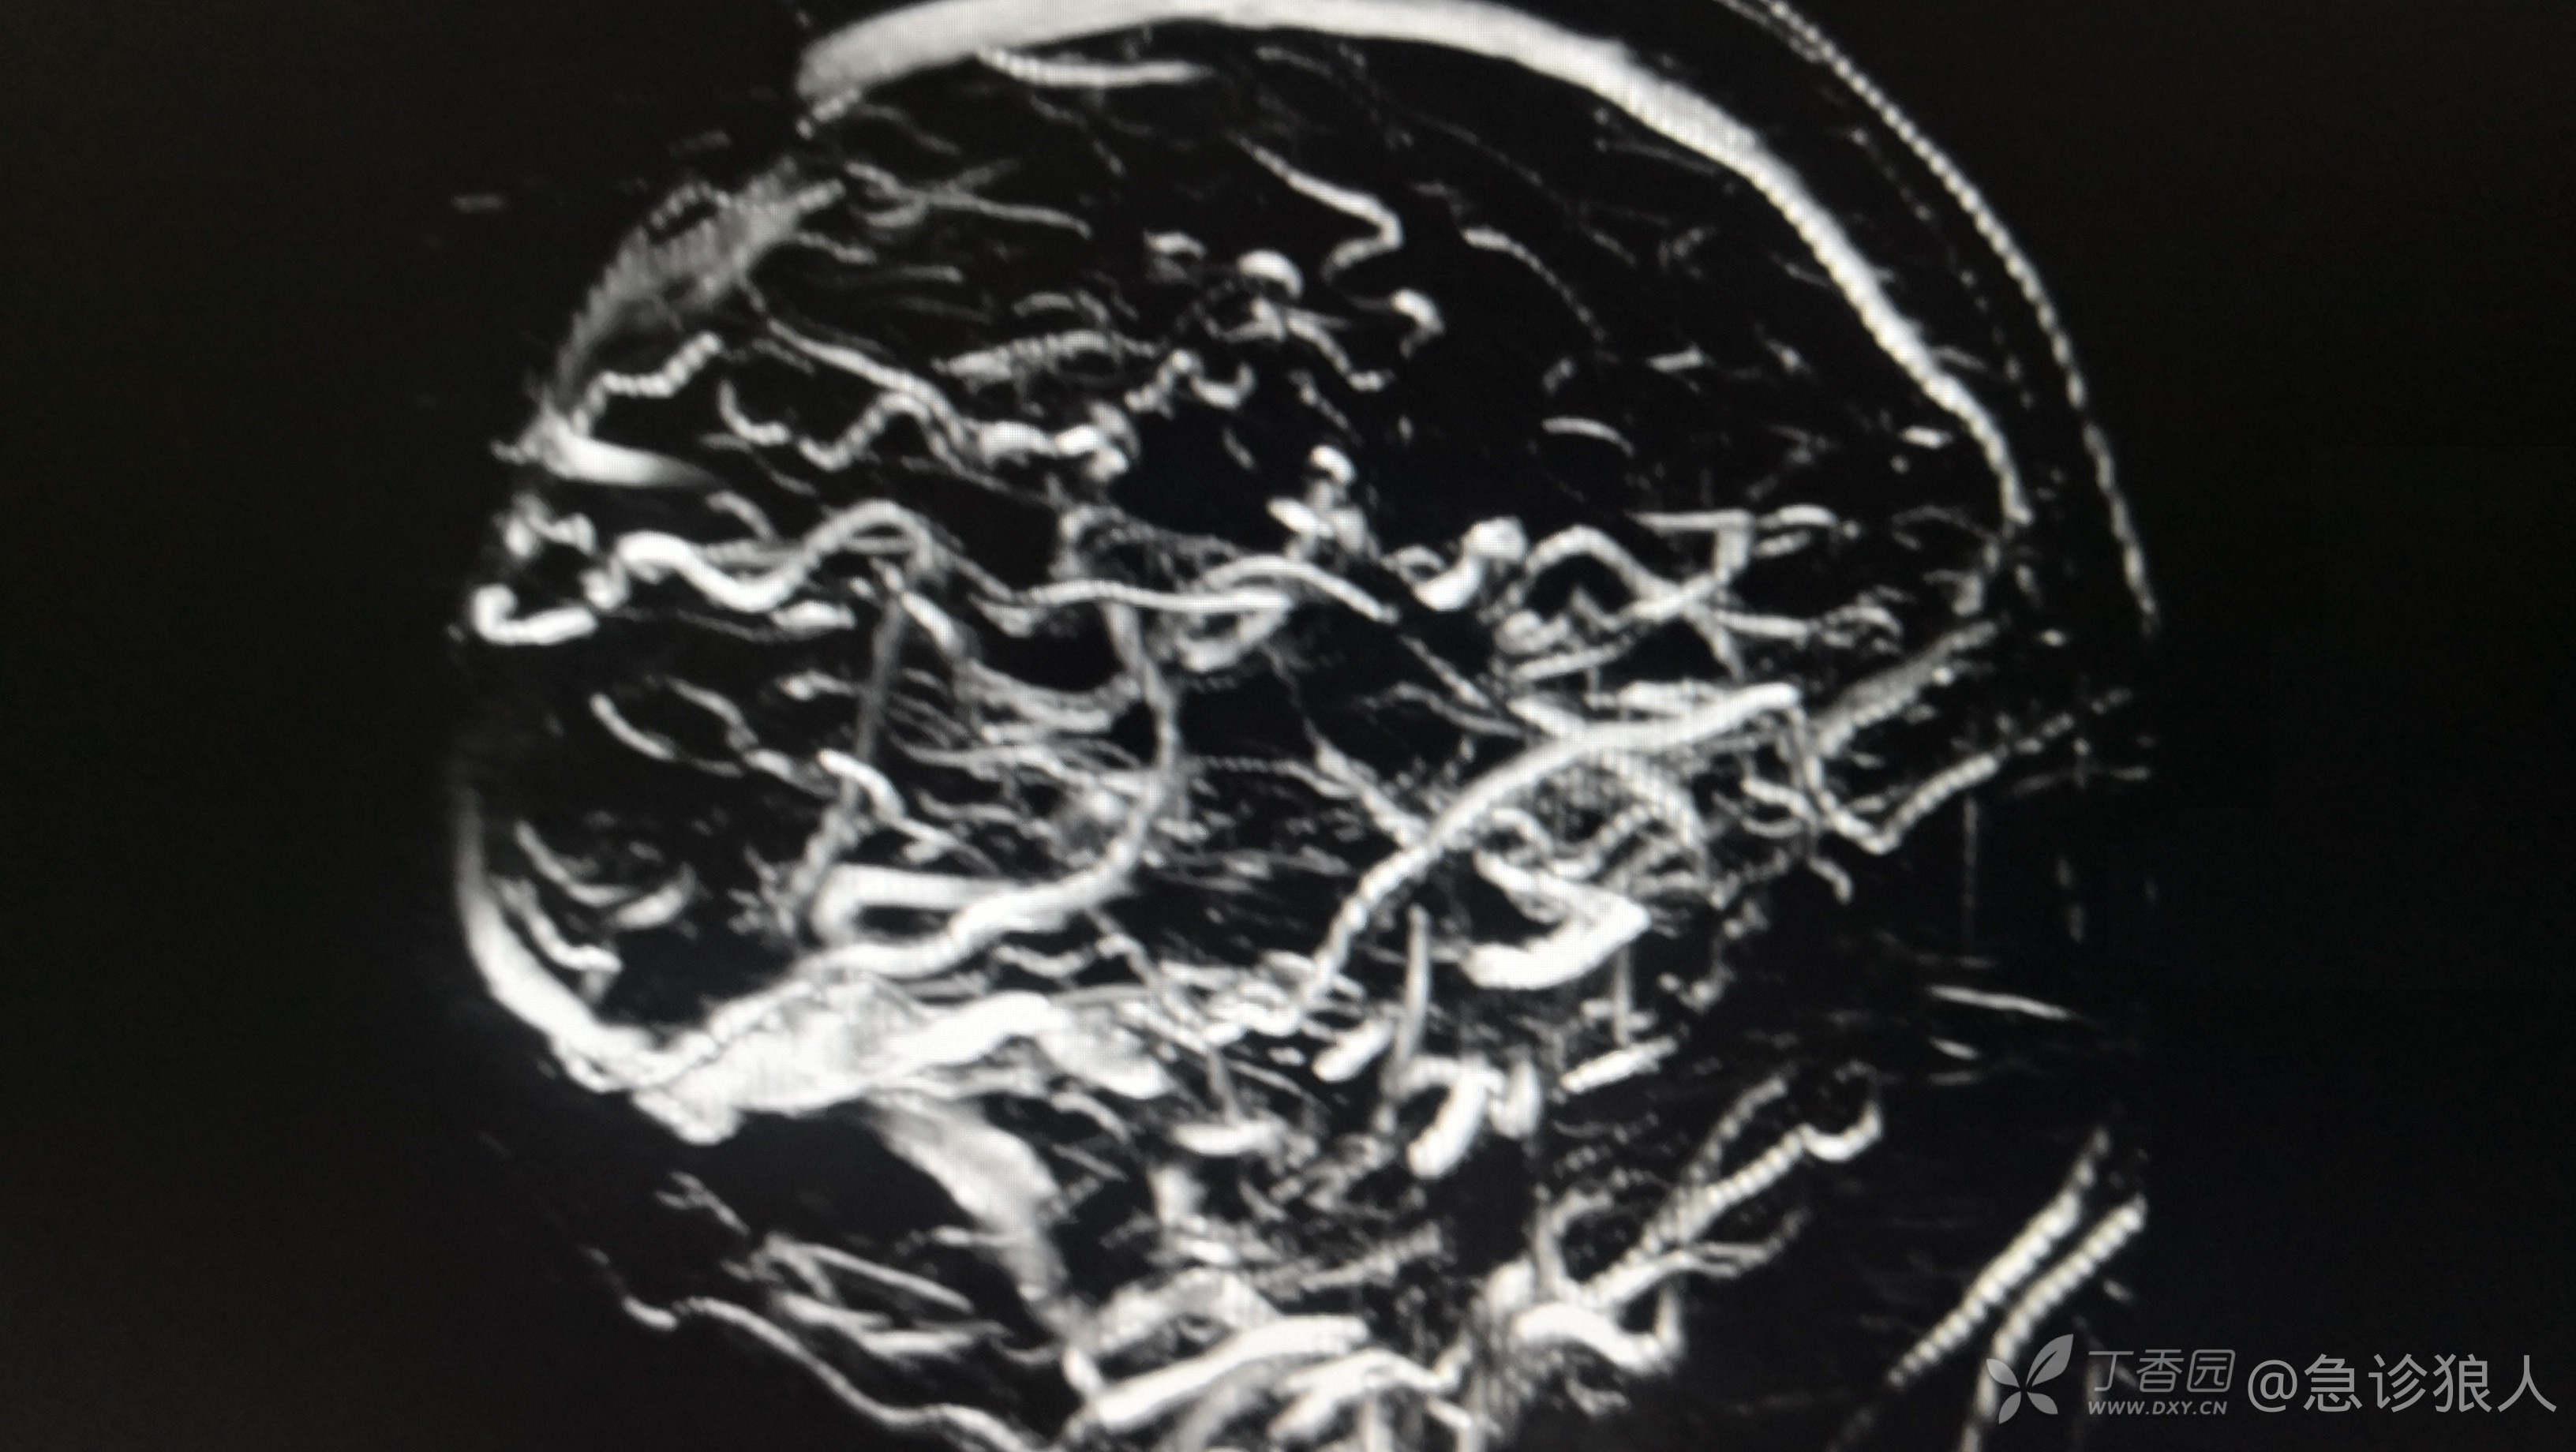

左侧大脑半球多发杂乱,迂曲血管影,与左侧乙状窦相通,考虑硬脑膜动静脉瘘可能性大。

出来结果,神内愿意收了,收上去做了DSA,动静脉瘘修补!